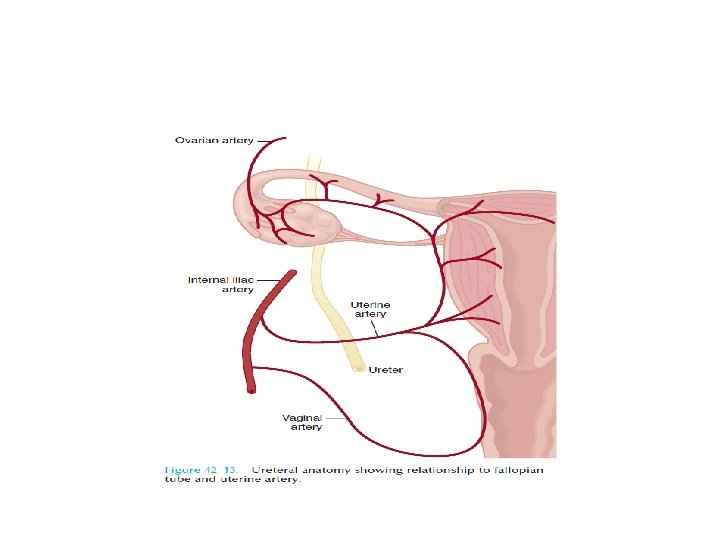

Ureteral Injury • No reliable Physical findings! Usually a retrograde diagnosis • Non specific symptoms – Flank pain (36%-90%) – Fever – Ileus – Abdominal distension – fistula

Etiology • External trauma – High speed blunt injuries – Penetrating trauma • Surgical injury – Gynecological – Obstetric – General surgery( colorectal sx) – Urologic procedures • Ureteroscopic injury

Diagnosis • Presense of hematuria(non specific) • Imaging – IVU – CT urogram – RGP – Antegrade ureterography • Intraoperative recognisation

Hematuria and ureteral injury • Nonspecific indicator • 25 – 45% patients donot demonstrate even microscopic hematuria. • Being suspicious for it is the only way you will catch it.